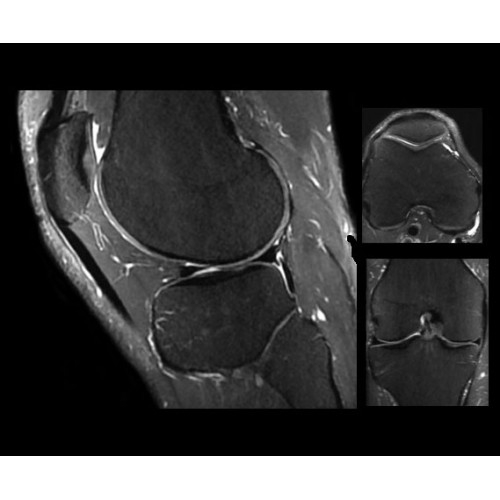

SIGNA PET/MR 3.0T — это гибридная система, в которой совмещаются две принципиально разные технологии — магнитно-резонансную томографию (МРТ) и позитронно-эмиссионную томографию (ПЭТ). Система отличающийся высокой чувствительностью и эффективностью и предназначена для диагностики в области онкологии, неврологии, кардио-васкулярных исследований, исследований воспалительных процессов.

Компания GE Healthcare представляет революционную, полностью интегрированную систему SIGNA PET/MR1, в которой сочетаются времяпролетная технология (TOF) и возможности напряженности магнитного поля 3.0 Тл. Мы поможем вам поднять исследования на более высокий уровень. SIGNA PET/MR позволяет достичь впечатляющей точности и скорости исследований, а благодаря новейшей технологии реконструкции Q.Clear2 качество изображений улучшается в два раза. Кроме того, в систему включен полный набор клинических приложений и гибких катушек для проведения любых видов исследования, открывая для вас возможности визуализации, о которых вы даже не догадывались.

Кроме того, в результате использования технологии TOF и инновационной технологии реконструкции Q.Clear вы сможете добиться прекрасного соотношения сигнал/шум. А благодаря технологии нулевого времени эхо (ZTE) визуализировать костную структуру без ионизирующего излучения. Все эти разработки для улучшения качества сканирования и точности анализа помогут вам использовать весь потенциал ПЭТ/МРТ.

Система SIGNA PET/MR предлагает впечатляющие клинические возможности и открывает доступ к наиболее полным пакетам программных приложений.

Стандартный пакет приложений SIGNA Works позволит вам достичь желаемых результатов в клинической практике благодаря набору высокоэффективных средств визуализации. Программные приложения, входящие в состав данных клинических пакетов, включают широкий спектр контрастов, функции обработки 2D- и 3D-данных, а также возможность коррекции артефактов движения. SIGNA Works предоставляет набор инструментов, необходимых для проведения эффективного клинического исследования.